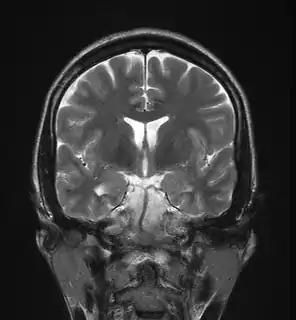

Hippocampal sclerosis

Hippocampal sclerosis (HS) is a neuropathological condition with severe neuronal cell loss and gliosis in the hippocampus, specifically in the CA-1 (Cornu Ammonis area 1) and subiculum of the hippocampus. It was first described in 1880 by Wilhelm Sommer.[1] Hippocampal sclerosis is a frequent pathologic finding in community-based dementia. Hippocampal sclerosis can be detected with autopsy or MRI. Individuals with hippocampal sclerosis have similar initial symptoms and rates of dementia progression to those with Alzheimer's disease (AD) and therefore are frequently misclassified as having Alzheimer's Disease. But clinical and pathologic findings suggest that hippocampal sclerosis has characteristics of a progressive disorder although the underlying cause remains elusive.[2] A diagnosis of hippocampal sclerosis has a significant effect on the life of patients because of the notable mortality, morbidity and social impact related to epilepsy, as well as side effects associated with antiepileptic treatments.[3]

| Mesial Temporal Sclerosis | |